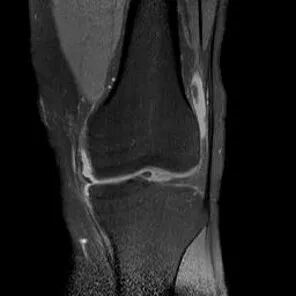

半月板撕裂定义与显示

1、半月板显示:以T2-WI加脂肪抑制为最好.2、半月板病变:最常见损伤是撕裂伤3、病因:慢性退变性撕裂和急性外伤性撕裂4、诊断方法:当半月板内出现线样高信号到达其游离缘或关节面时,即可诊断半月板撕裂5、病变信号变化:T1WI为线样稍高信号,T2(FS)或T2*WI信号更高6、半月板球形及线行高信号影未达关节面,为其慢性损伤或退行性改变(变性)7、MR诊断半月板撕裂的准确度达90-97%,特异性为94%,假阳性高于假阴性,主要是将膝横韧带与外侧半月板相邻的国肌腱鞘等误认为半月板撕裂.